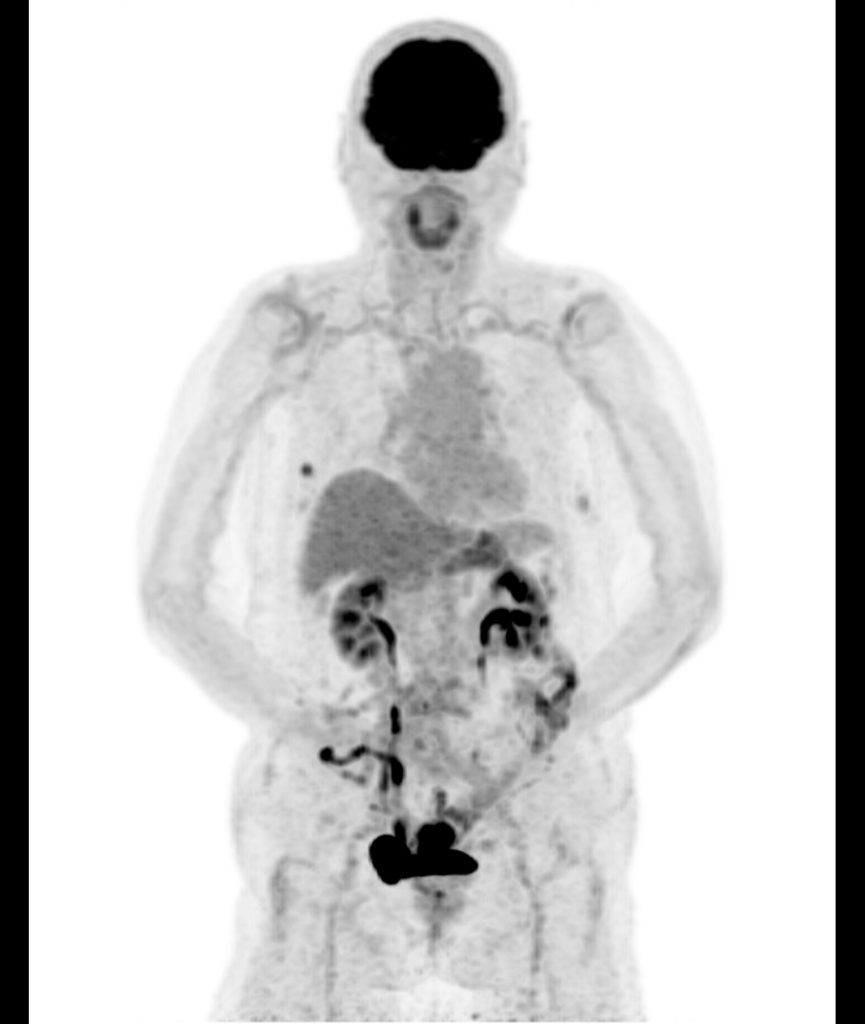

放射線画像診断科は、がん診療の最前線で重要な役割を担っています。がん治療において、病期診断(ステージング)は治療方針を決定する上で欠かせない情報です。当科では、CT、MRI、PETなどの最新の画像診断機器を駆使し、がんの進行度や転移の有無を正確に評価しています。特にPET検査は、がん細胞の活動を画像化できるため、全身の状態を把握するうえで非常に有効です。

たとえば、胃がんや大腸がんでは、リンパ節転移や肝転移、腹膜播種の有無が治療戦略に大きく影響します。CTによる腹部全体の精査や、MRIによる局所の質的評価、必要に応じたPETによる全身検索などを組み合わせ、病変の広がりを多角的に把握しています。これにより、手術適応の判断や化学療法の選択など、治療の方向性をより確かなものにすることができます。

さらに、シーメンス社製のPET装置を用いた全身スキャンでは、がん細胞の活動性を捉える分子レベルの画像診断が可能となり、がん診療において極めて重要な役割を担っています。